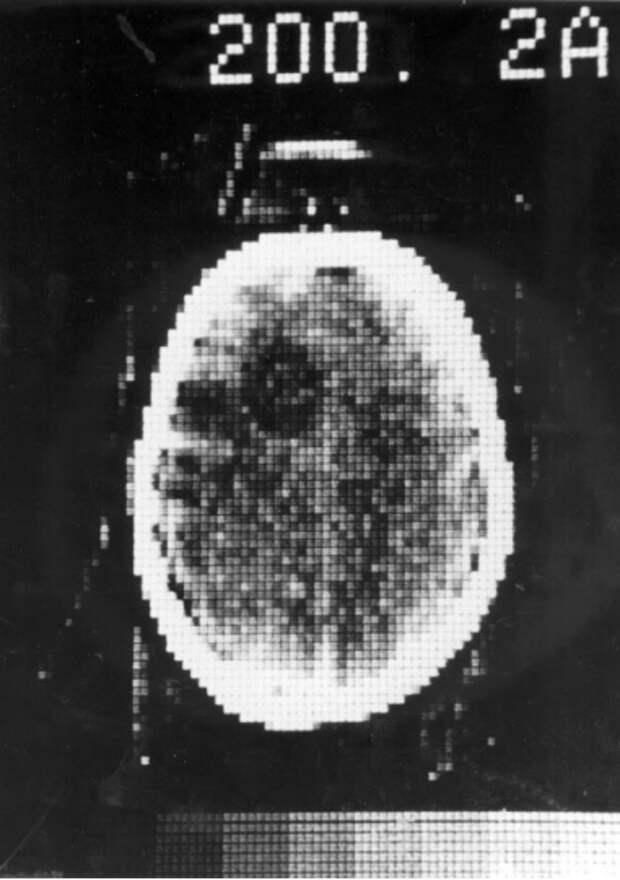

Тем не менее оставалось проверить, насколько хорошо машина сможет отличать норму от патологии. Для этого в 1971 году в госпитале Аткинсона Морли в Уимблдоне сконструировали первый клинический компьютерный томограф, и началось исследование больных с опухолями и другими заболеваниями головного мозга. В 1972 году появилась первая сканограмма головного мозга женщины с подозрением на его поражение, и полученное изображение отчетливо показало наличие темной округлой кисты.

Первая КТ пациента